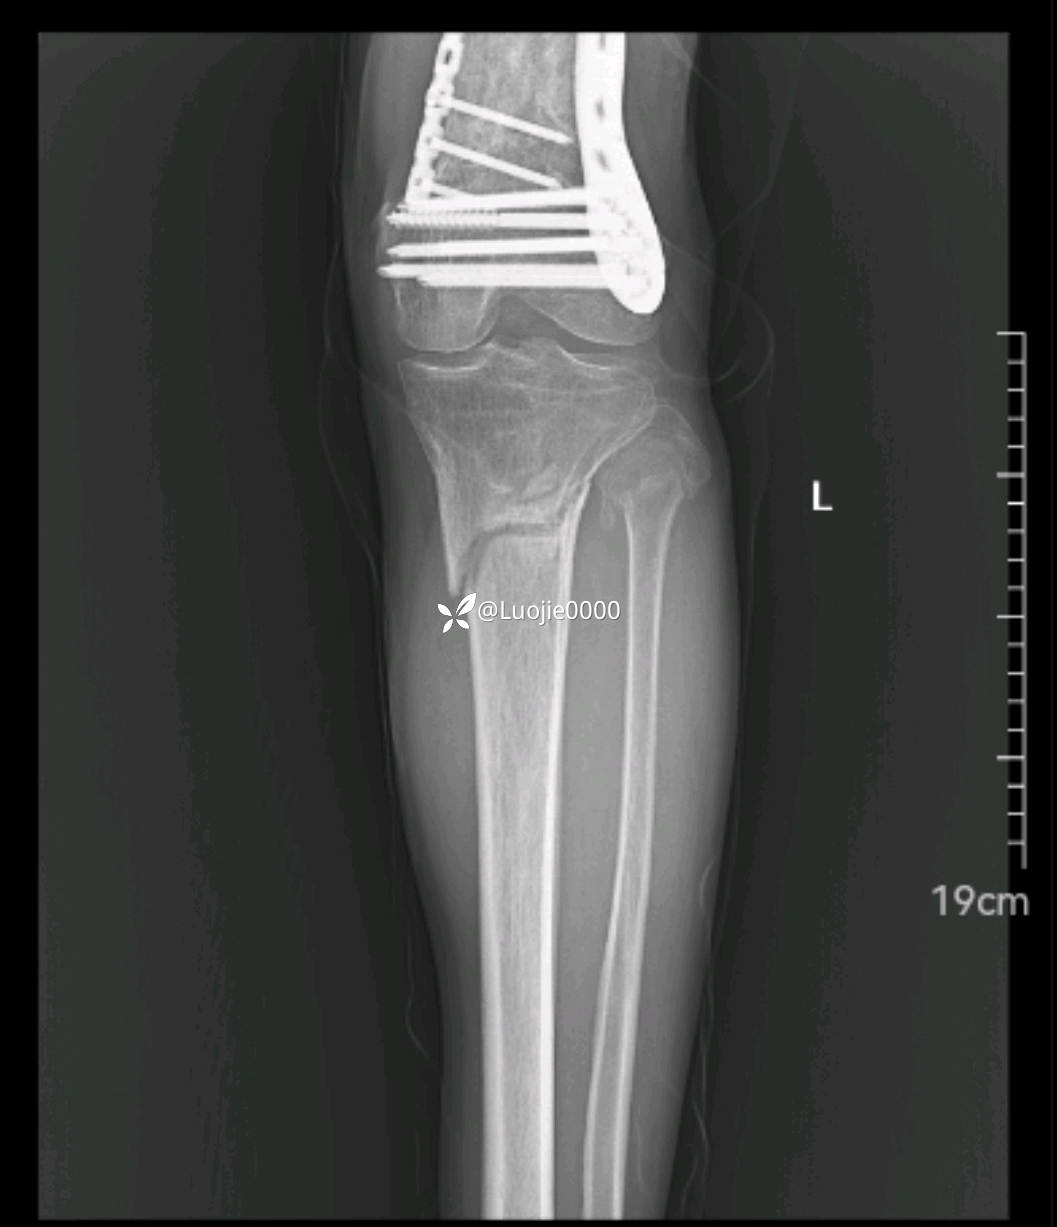

辅助检查:DR及CT提示:左胫骨近端及腓骨头骨折。

影像资料如下: